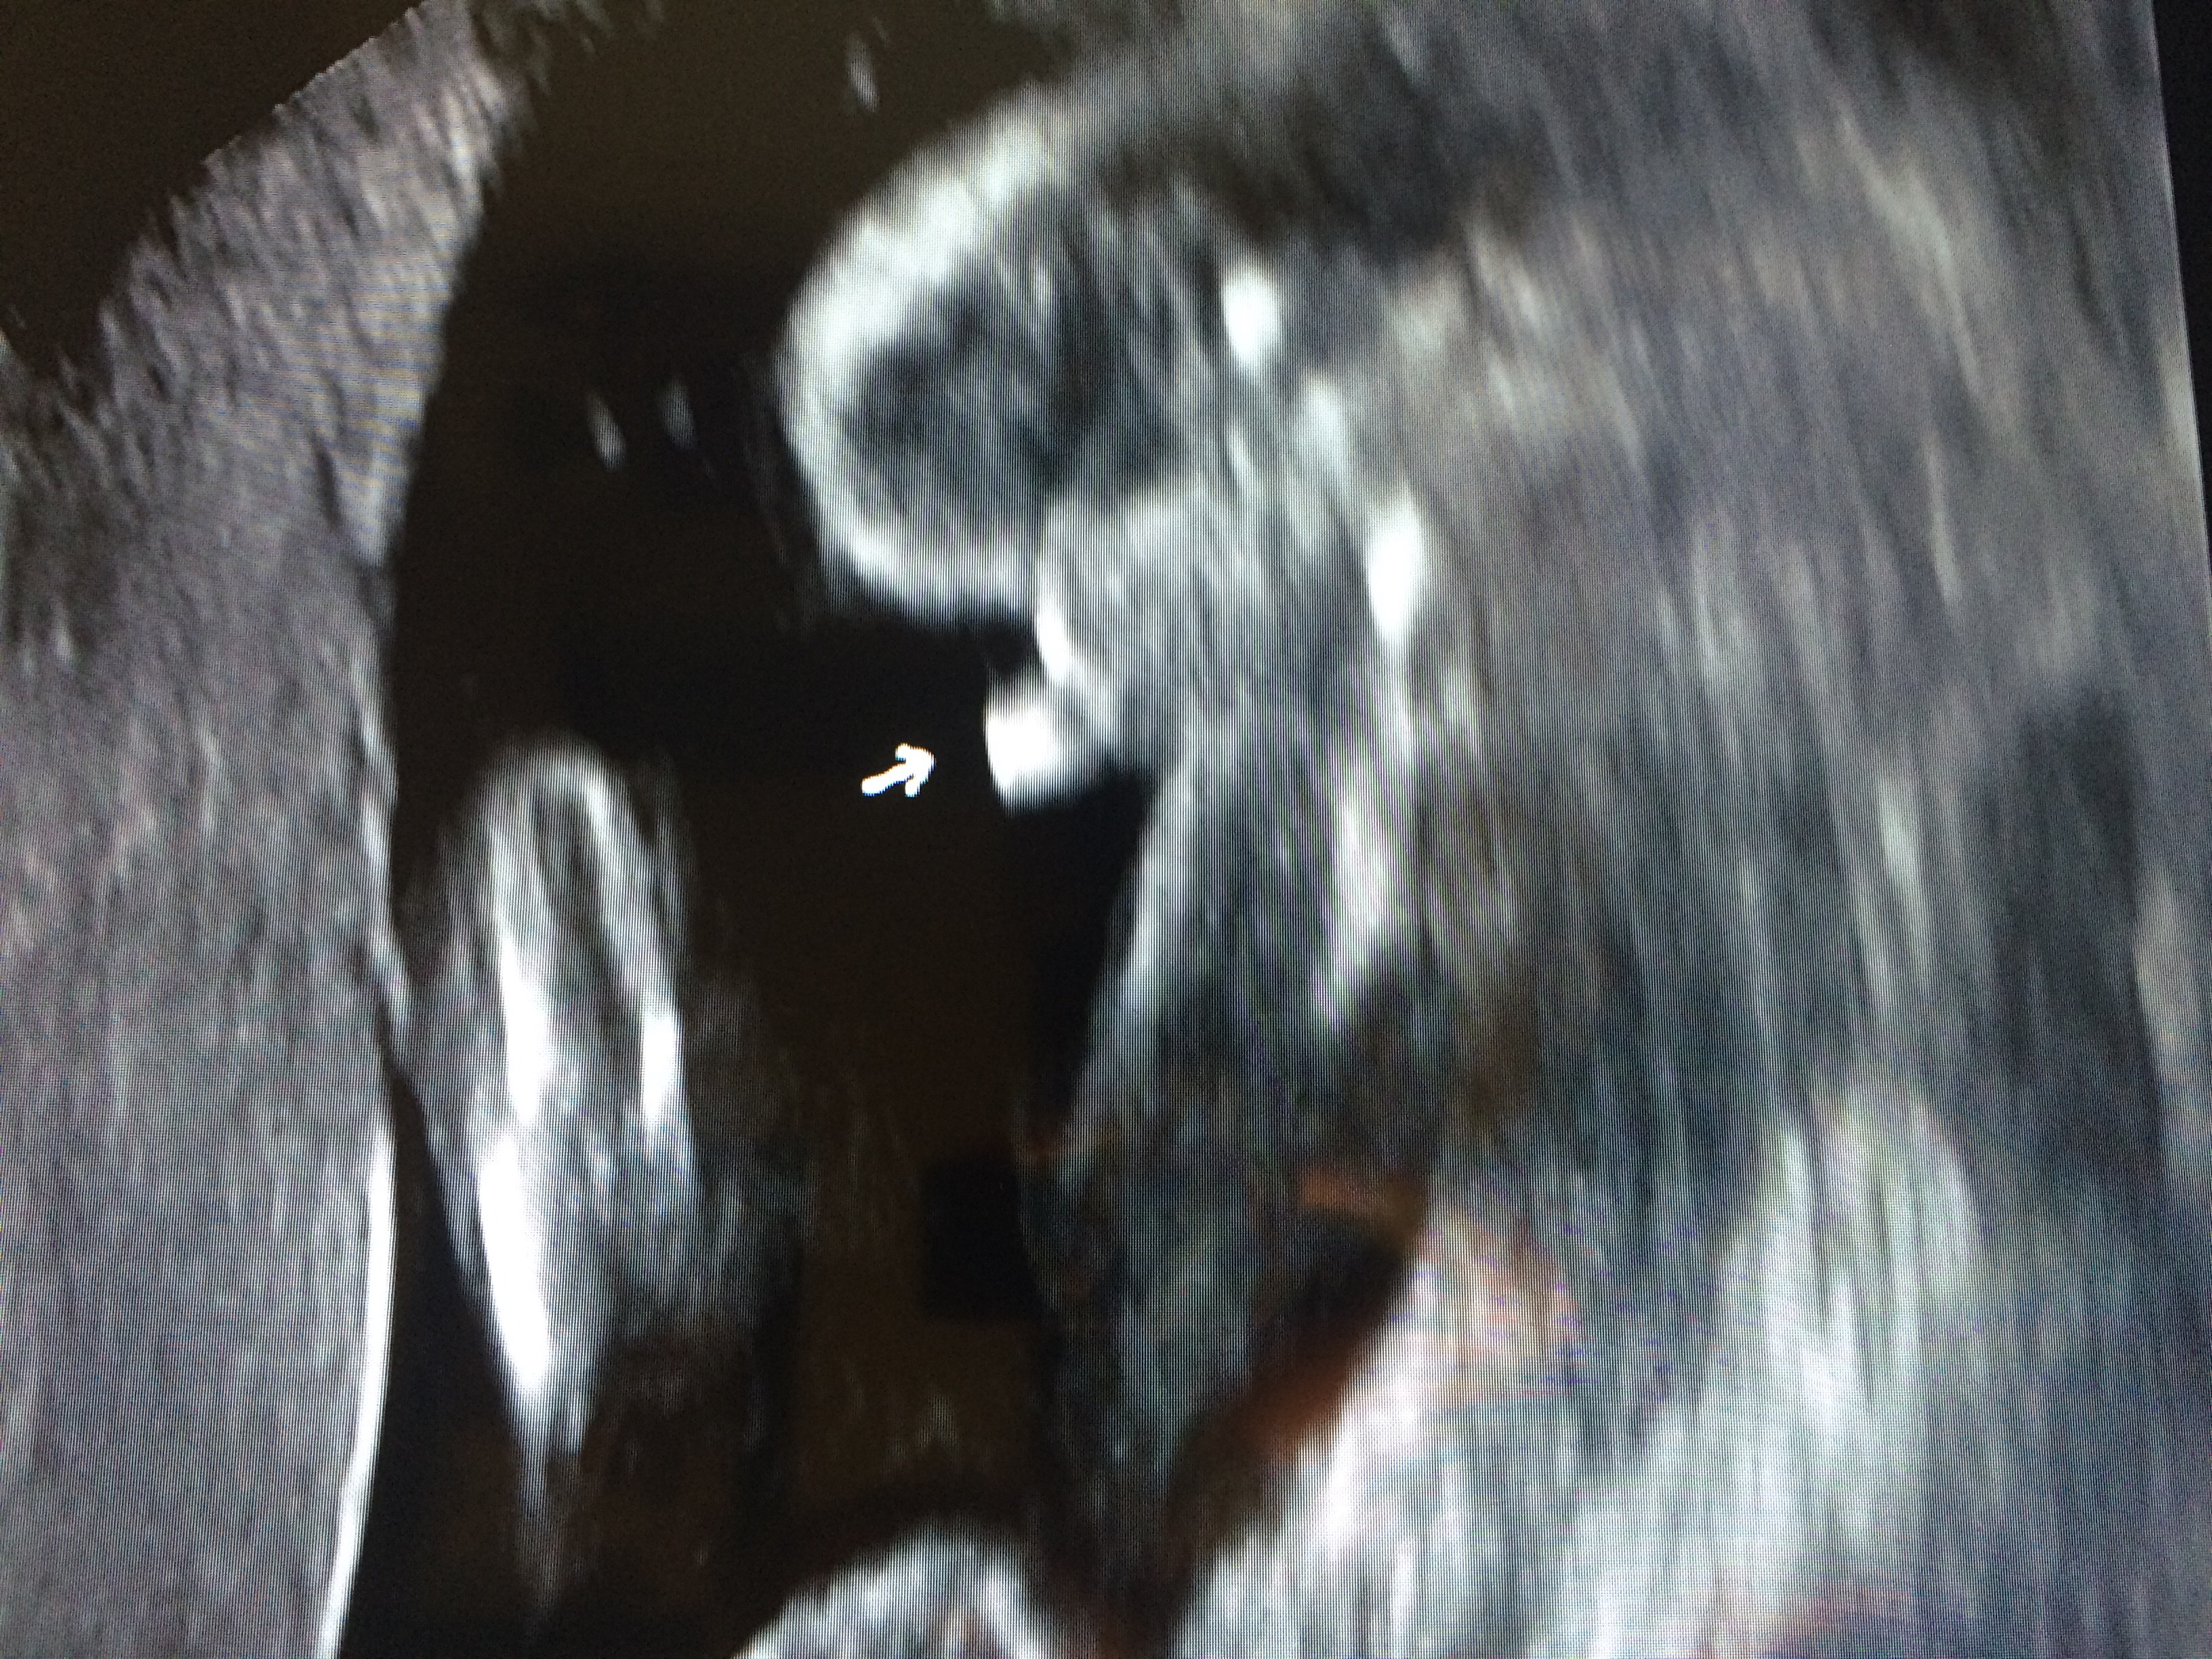

Had our ultrasound yesterday and we are adding another healthy little boy (no question about it) to our family. That will give us boy-girl-boy. The boys have us outnumbered but they will be our protectors. Due the 11th but usually go late. Go team blue!!

It's a BOY!!!! His 2 big sisters can't wait to meet him. He was active, healthy, but a bit small, so he is now due on New Years Day. We could not be happier!!!

I'm officially on TEAM BLUE!!